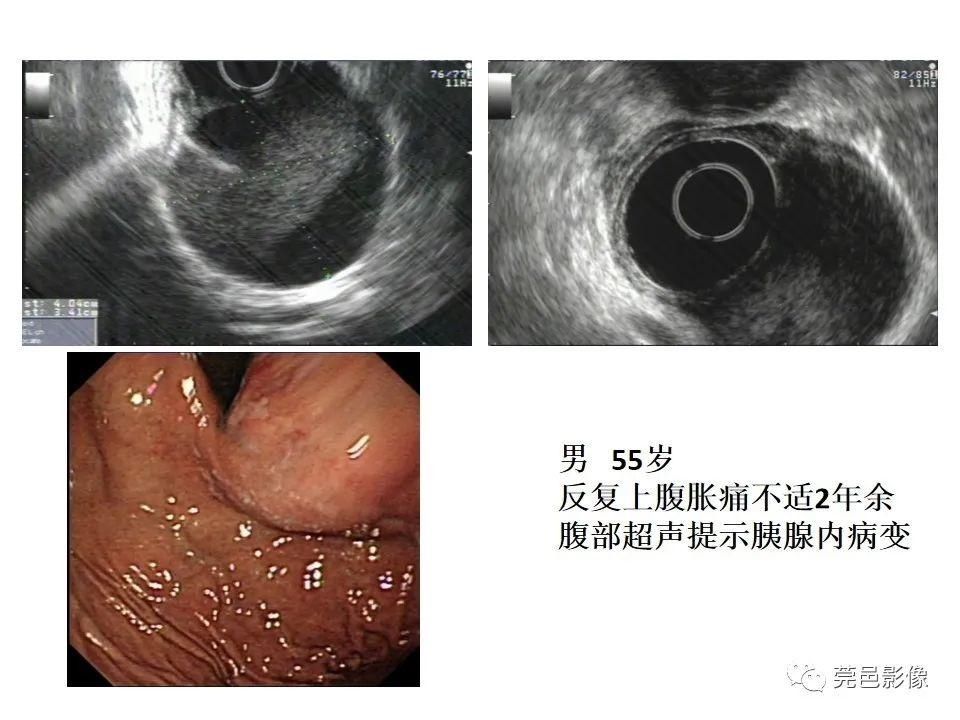

典型表现:“内衬黏膜,外绕平滑肌”;胃壁五层结构内的低回声或无回声病

灶,多位于粘膜下层,与正常胃壁共有平滑肌层或浆膜层;内衬黏膜产生特征性的高回声,相邻的外绕平滑肌层则为低回声,从而构成胃重复囊壁的“双层征” (50%);有时超声下可见重复畸形囊壁的蠕动收缩改变(良好的平滑肌),该征象有助于同肠系膜囊肿、卵巢囊肿等腹腔囊性肿块鉴别;少数与胃腔相通的管状重复畸形,EUS下可见其收缩蠕动,是胃重复畸形的佐证